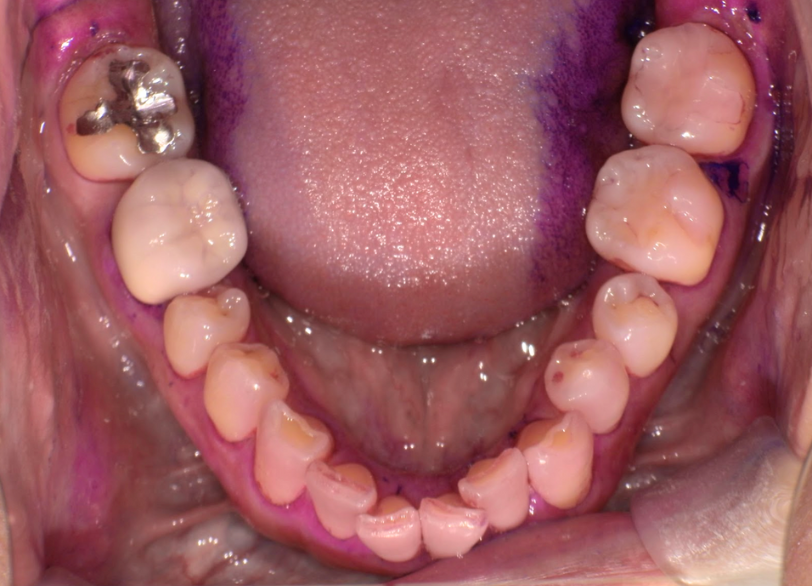

術前 右上7の銀歯

術後 右上7の銀歯がセラミックに置き換わっている(1.5時間で銀歯の除去からセラミック装着まで完了)

歯と歯の間にもう蝕があり2本同時に1日で銀歯除去からセレック置き換え治療を行った